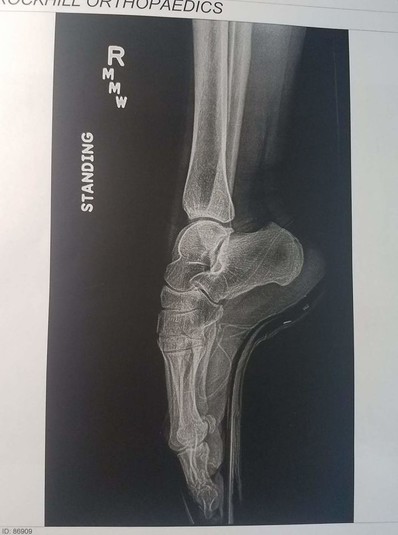

Подборка рентгеновских снимков, которые наглядно показывают, что от нас скрывает природа

Самые занимательные рентгеновские снимки, показывающие, что скрыто от глаз человека

Сегодня открытие немца используют во многих сферах жизни, начиная с медицины и заканчивая таможней. Собрали для вас самые занимательные рентгеновские снимки, показывающие, что скрыто от глаз человека.